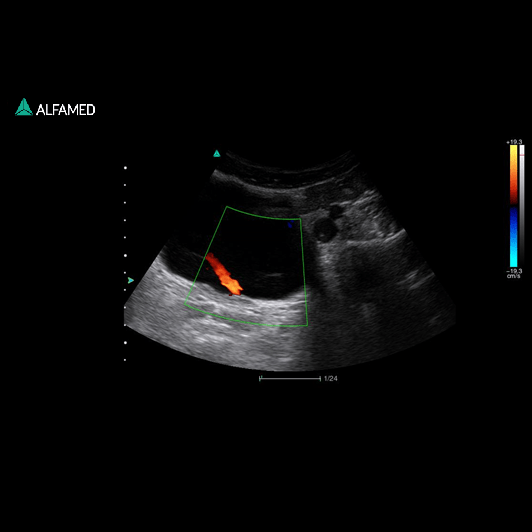

⦁ Modo B, 2B, 4B, M, Power Doppler Direcional, CW, M, PW; B/M, CFM, B/C,

PWD, CPA, DPA, B+CFM, B+CPA, B+DPA, B+PW, B+CFM+PW, B+CPA+PW,

Triplex/Duplex;